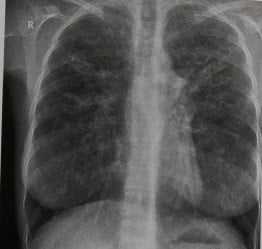

Муковисцидоз у женщины 34 лет. Помимо нерезко выраженного усиления воздушности легких на рентгенограмме грудной клетки виден тяжистый рисунок, охватывающий все легочное поле и особенно выраженный в верхнем и среднем его отделах. Корни легких укорочены и смещены кверху. Эти признаки обусловлены выраженными изменениями бронхиальной стенки и бронхоэктазами.

КТ более информативна для определения типа и объема изменений. На срезах, проходящих через легкие, видны многочисленные кистовидные и мешотчатые бронхоэктазы